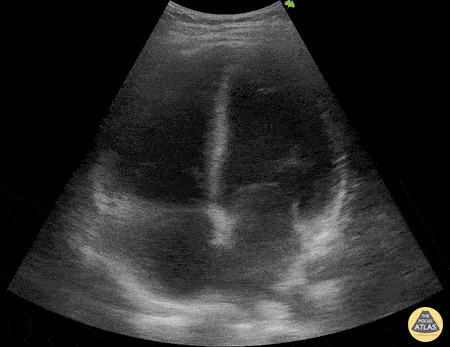

A 29-year-old patient, with a recent history of mild COVID 19 infection, consulted for a 5-day history of fever, associated with abdominal pain, arthralgia and myalgia. Hypotensive on admission (80/50 mmHg), with HR 100 bpm and echocardiography performed with a convex transducer: LVEF 12%, with global hypokinesia and dilated cavities. The diagnosis of post-COVID myocarditis is made. Dr. Libardo Valencia Chicué